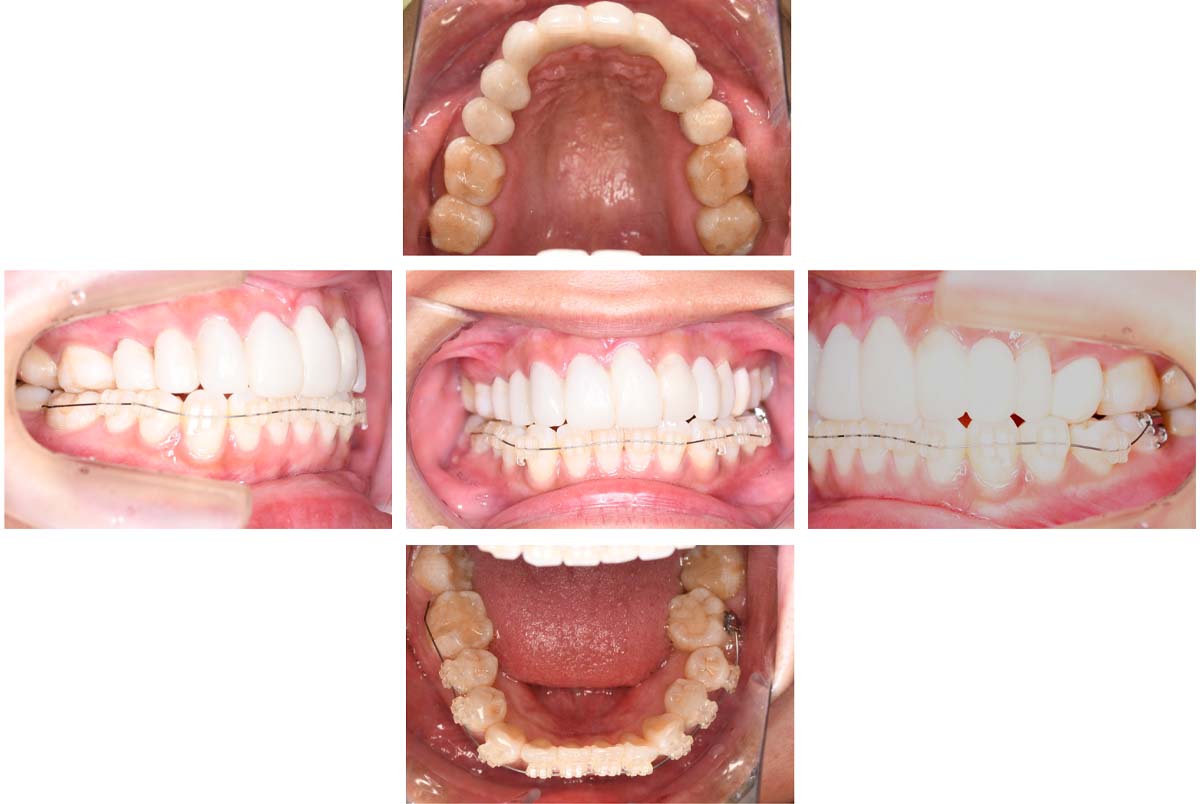

副子なし 副子あり

バイトアップ後

2024年 10月 下顎MTM開始

2024年 10月10日